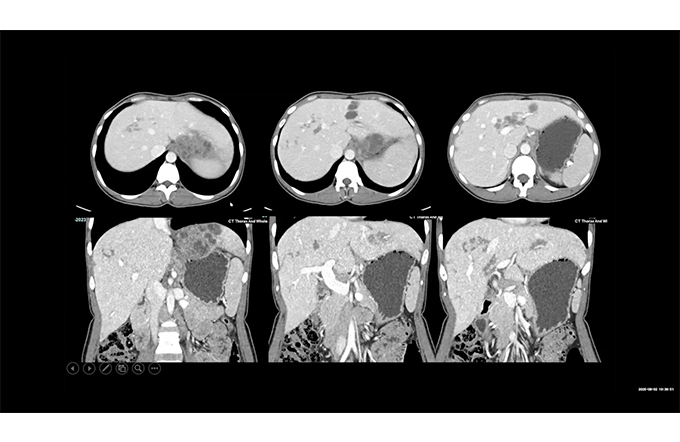

Case based Neuro and Head & Neck Discussion